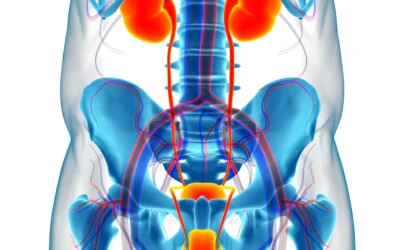

L’adénome de la prostate

et sa prise en charge par énucléation prostatique au laser (HoLEP)

La dysfonction érectile

et sa prise en charge par des implants péniens gonflables.

L’incontinence urinaire masculine modérée

et sa prise en charge par bandelette de soutènement sous urétral ou par sphincter artificiel urinaire.

L’incontinence urinaire masculine majeure